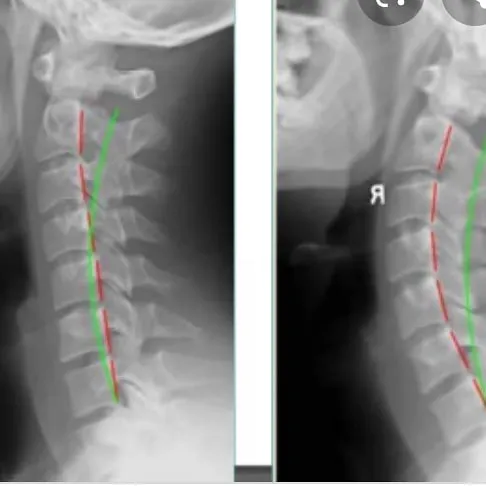

- Effective treatment for Text Neck